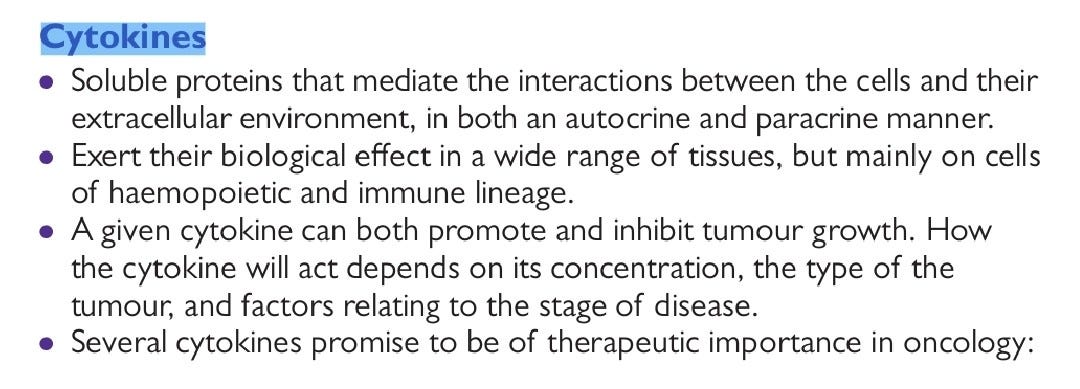

He could start by referring back to an Oncology 101 text book, for example this one, please go to page 190 Jerome: